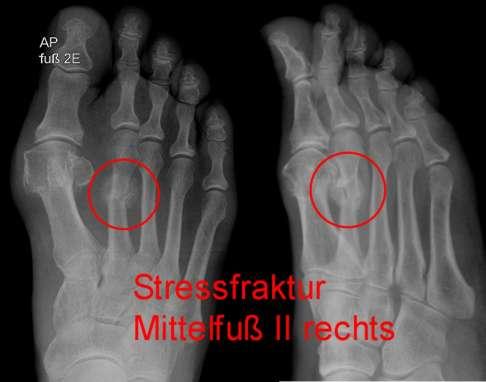

Eine Differentialdiagnose ist wichtig, um einen Ermüdungsbruch von anderen Erkrankungen zu unterscheiden. Dazu kann es notwendig sein, weitere bildgebende Verfahren wie Röntgenaufnahmen oder Magnetresonanztomographie (MRT) einzusetzen.

Bei Verdacht auf einen Ermüdungsbruch kann die DVT helfen, die Diagnose zu bestätigen oder auszuschließen. Typische Veränderungen am Mittelfuß, wie Knochenödeme oder geschädigte Knochensubstanz, können mit diesem Verfahren sichtbar gemacht werden.

5. Knochenbruch: Ein Knochenbruch kann durch eine Verletzung oder einen Unfall verursacht werden und ähnliche Symptome wie ein Ermüdungsbruch verursachen. Eine Röntgenuntersuchung kann helfen, einen Knochenbruch von einem Ermüdungsbruch zu unterscheiden.